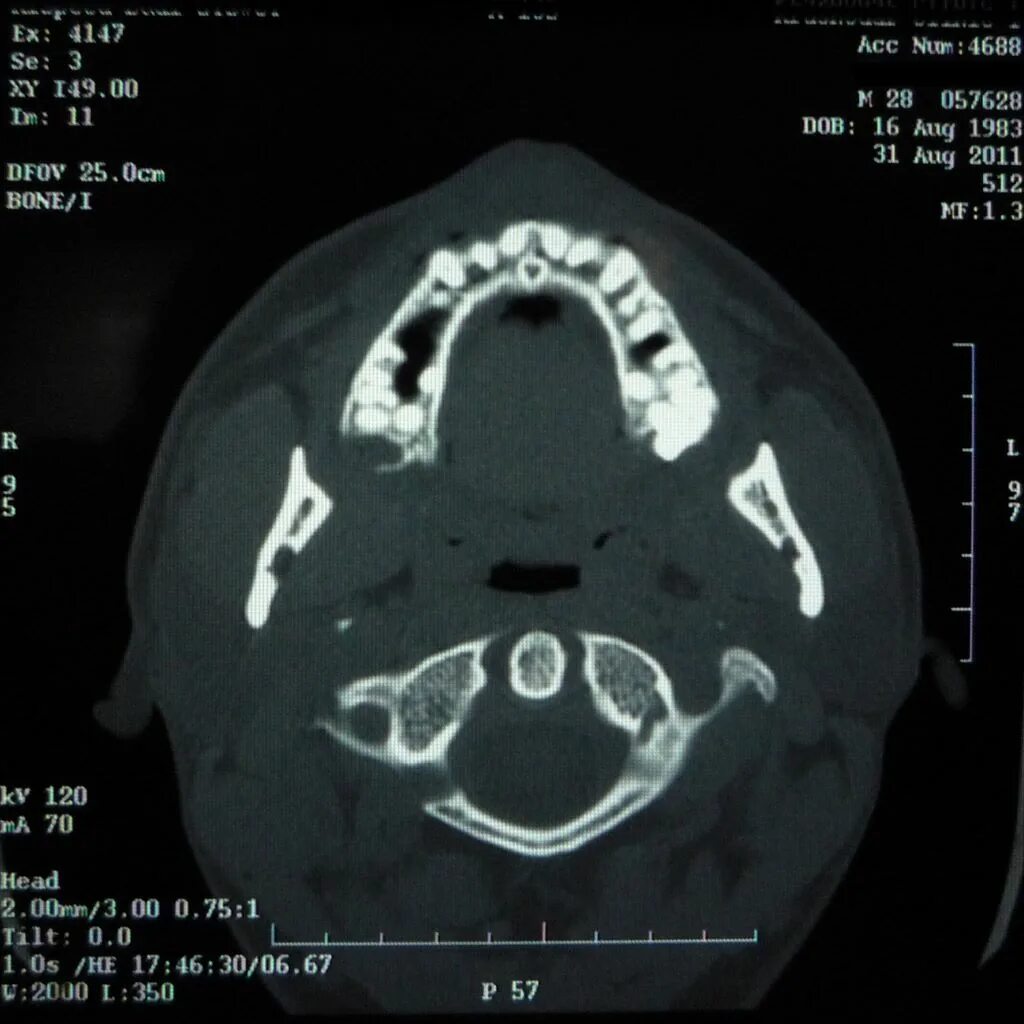

Череп на кт